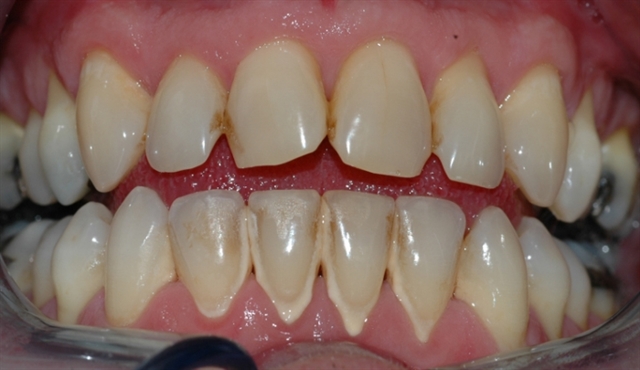

• Biletet viser eit tannsett med synleg tannstein og misfarging.